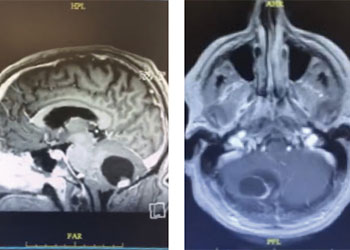

Neurosurgeons Collaborate to Treat Giant Symptomatic Meningioma

Author: Ramin Rak M.D., F.A.A.N.S., F.C.N.S., Jonathan L. Brisman M.D., F.A.C.S., Read More!

Cerebellar Hemangioblastoma

Author: Michael Brisman M.D., F.A.C.S., Read More!